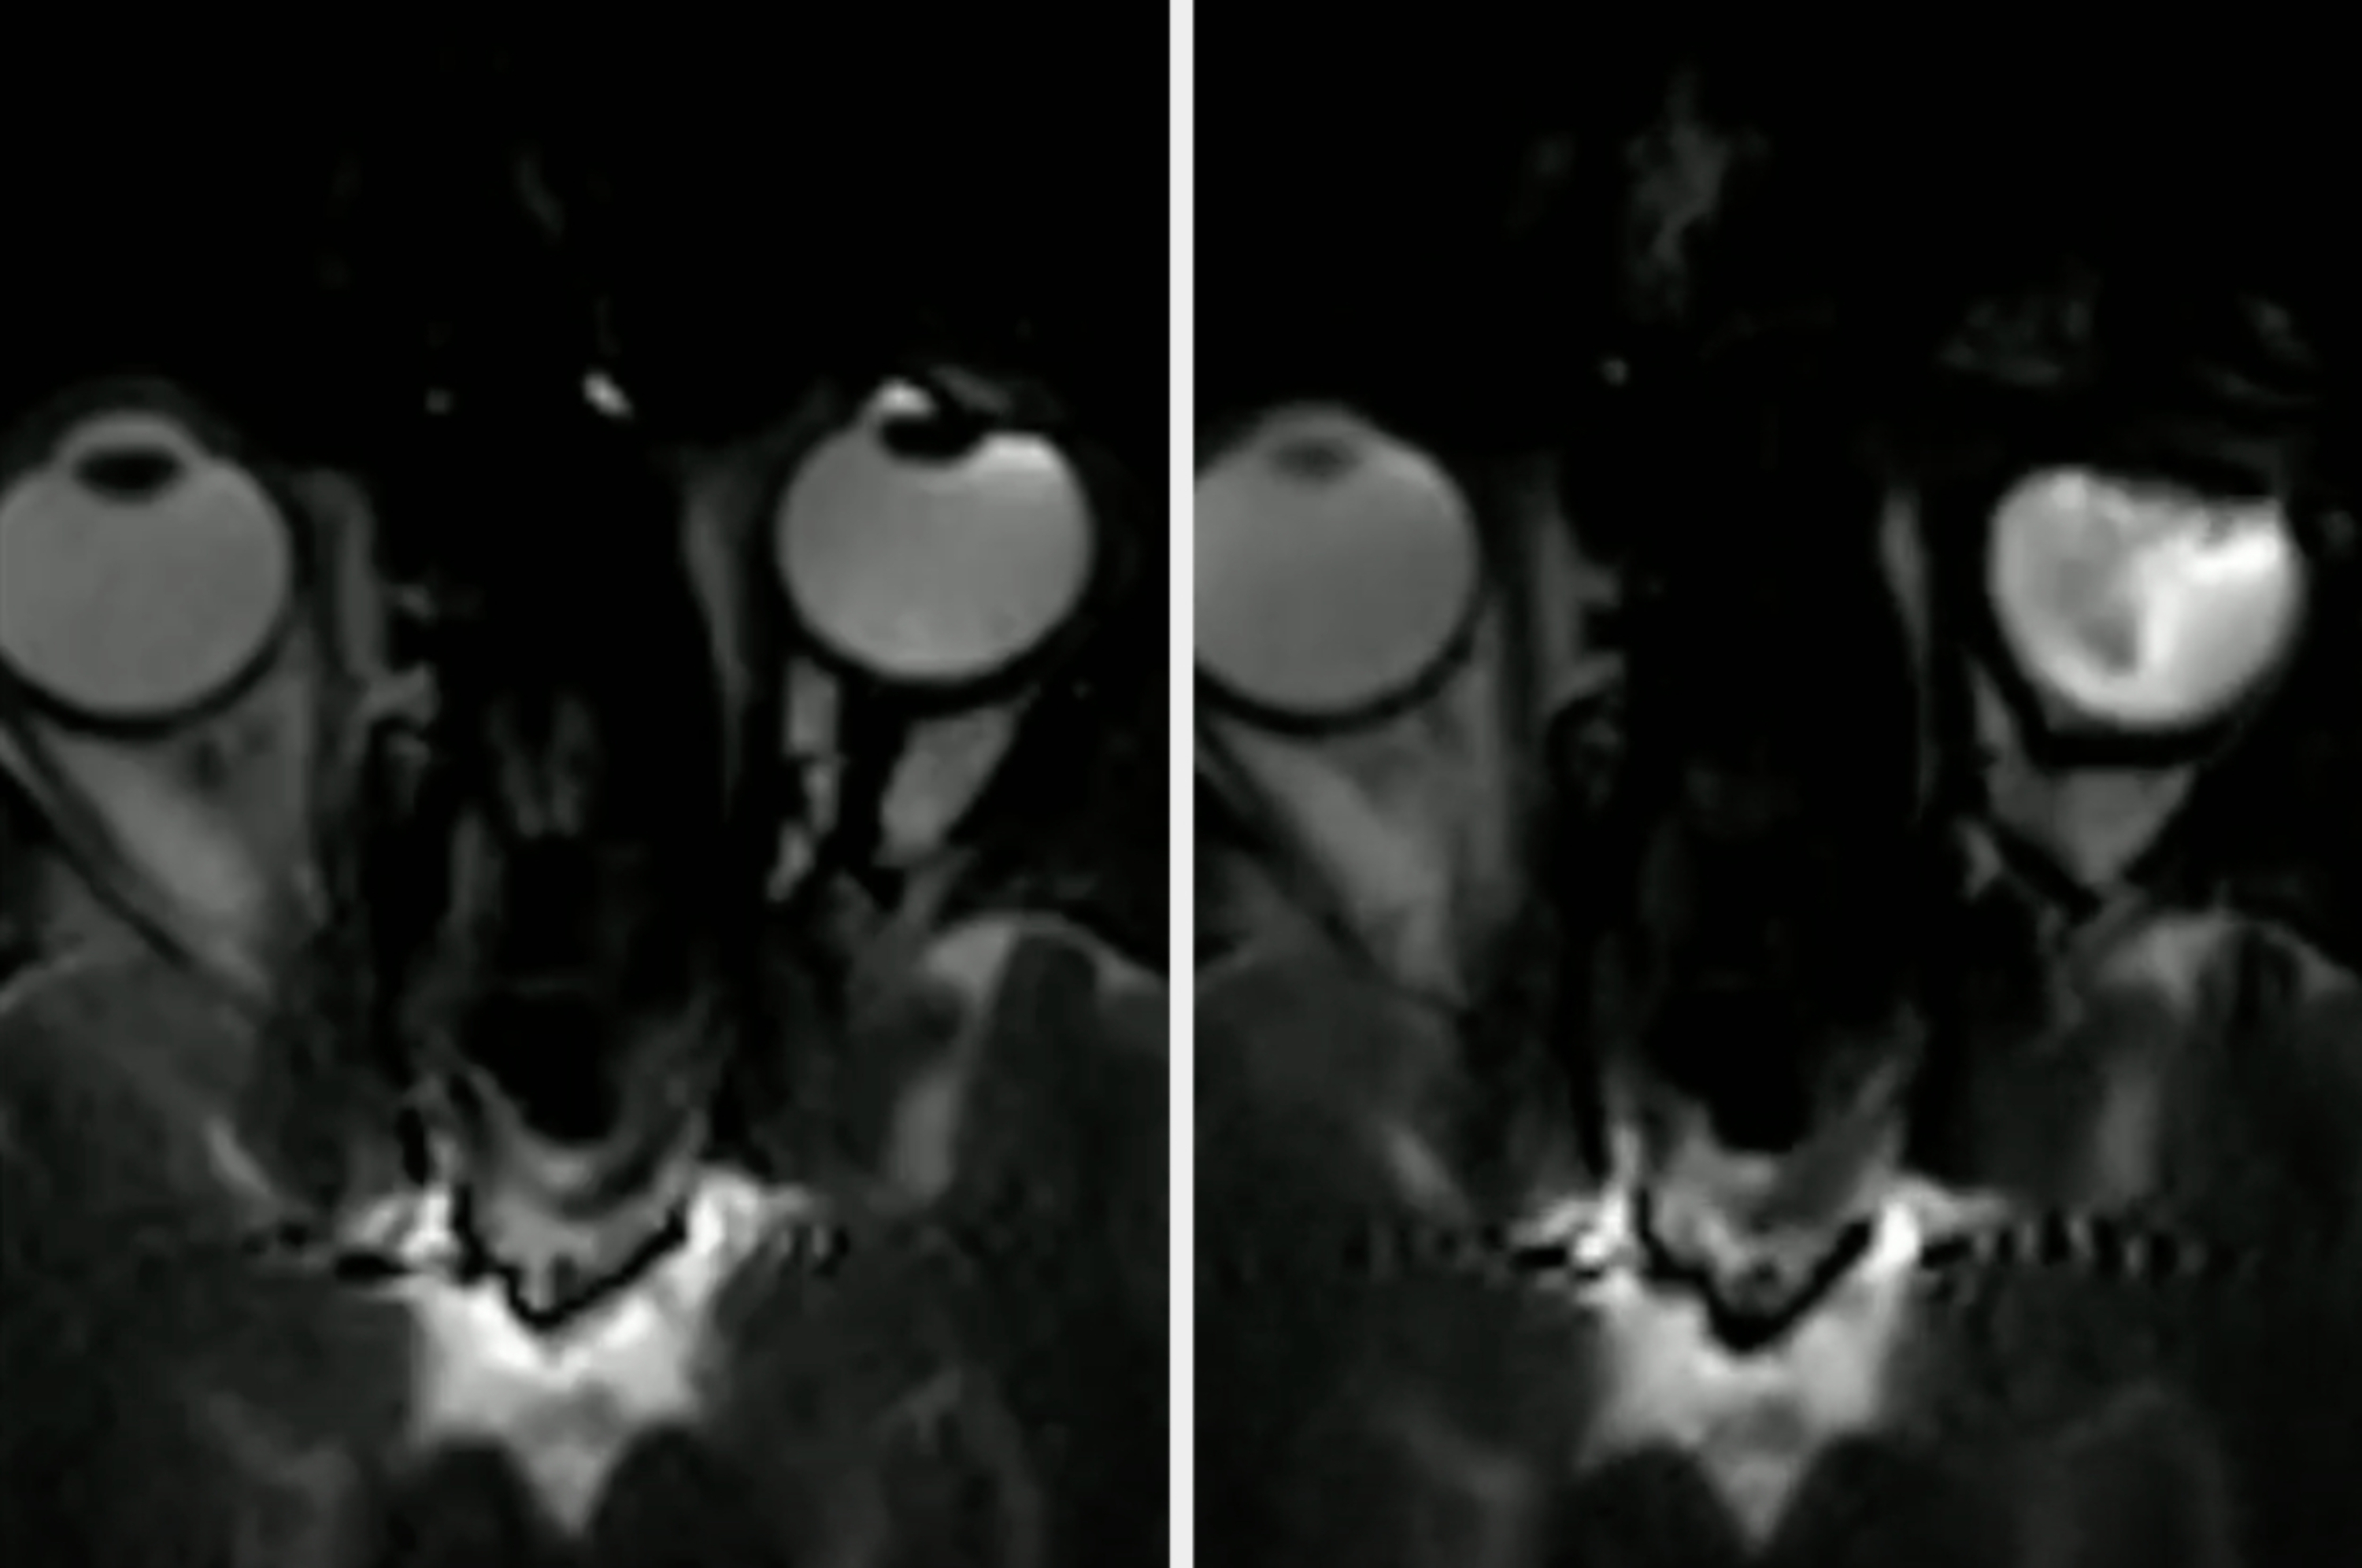

8.“How your eye looks when you rub it (MRI)":